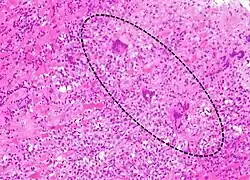

| A microscope image of myocarditis at autopsy in a person with acute onset of heart failure. The black dots are primarily lymphocytes infiltrating the myocardium. | |

Most forms of myocarditis involve the infiltration of heart tissues by one or two types of pro-inflammatory blood cells, lymphocytes and macrophages plus two respective descendants of these cells, NK cells and macrophages. Eosinophilic myocarditis is a subtype of myocarditis in which cardiac tissue is infiltrated by another type of pro-inflammatory blood cell, the eosinophil. Eosinophilic myocarditis is further distinguished from non-eosinophilic myocarditis by having a different set of causes and recommended treatments.[36][20]

The gold standard is the biopsy of the myocardium, in general done in the setting of angiography. A small tissue sample of the endocardium and myocardium is taken and investigated. The cause of the myocarditis can be only identified by a biopsy. Endomyocardial biopsy samples are assessed for histopathology (how the tissue looks like under the microscope): myocardial interstitium may show abundant edema and inflammatory infiltrate, rich in lymphocytes and macrophages. Focal destruction of myocytes explains the myocardial pump failure.[12] In addition samples may be assessed with immunohistochemistry to determine which types of immune cells are involved in the reaction and how they are distributed. Furthermore, PCR and/or RT-PCR may be performed to identify particular viruses. Finally, further diagnostic methods like microRNA assays and gene-expression profile may be performed.